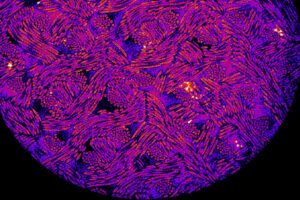

Many inflammatory disorders are linked to an overactive NLRP3 inflammasome due to increased cell death and production of inflammatory cytokines. In some cases, targeting the pyroptosis (an inflammatory form of cell death) pore forming unit GSDMD alleviates these disorders, but the direct role of GSDMD during sustained NLRP3 inflammasome activation is unclear. Using various knockout […]